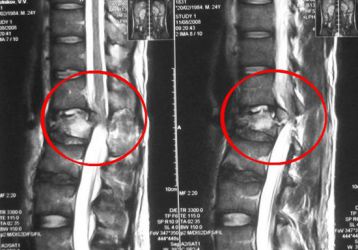

Медикаментозное и хирургическое лечение остеопороза поясничного отдела позвоночника

Способы лечения симптомов остеопороза поясничного отдела позвоночника. Гимнастика, медикаменты, физиотерапия и хирургические методы.